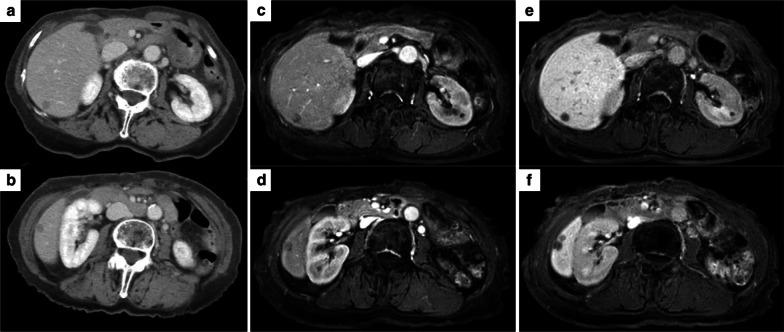

The patient was a 71-year-old woman who underwent distal pancreatectomy for solid pseudopapillary neoplasm, and liver metastasis occurred 4 years after the first surgery. Partial liver resection was performed for four liver metastases, and histopathological examination revealed a diagnosis of liver metastasis from solid pseudopapillary neoplasm. However, 18 months later, liver metastases were detected again; three tumors were identified, and partial resection was performed, which has provided 18 months' recurrence-free survival.

患者为一名71岁女性,因胰腺实性假乳头状瘤接受了远端胰腺切除术,首次手术后4年发生肝转移。对4处肝转移灶进行了部分肝切除,组织病理学检查确诊为胰腺实性假乳头状瘤肝转移。然而,18个月后再次检测到肝转移;发现3个肿瘤,并进行了部分切除,患者已获得18个月的无复发生存期。